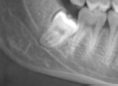

Figure 1. Developing tooth #32 preventing normal eruption of #31.

There is limited space. Wisdom teeth may contribute to crowding of teeth, prevent eruption of second molars and may cause shifting of teeth after braces.1